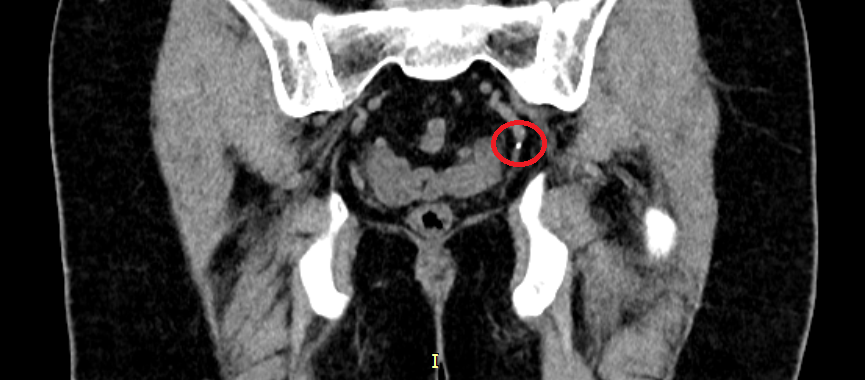

Сделал утром КТ по назначению уролога, так как месяц назад попал в неотложку с камнем в почке. Тогда на КТ он был 2х5мм, сейчас 3х7мм.

Но не в нем дело. А в других ярких точках в тазу (одна особо крупная и яркая), о которых в заключении радиолога ни полслова.